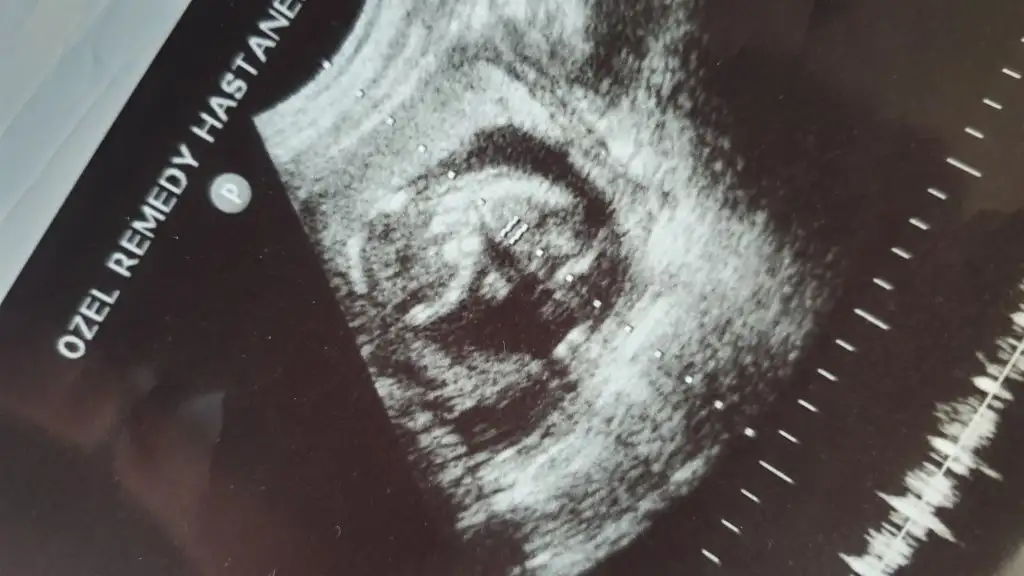

Bunlar bu günden en son da belli etmemişti yine belli etmemiş mi bakalım:)

Eklentiler

• 20200317_145448.webp

20200317_145448.webp

14,3 KB · Görüntüleme: 37

• 20200317_145431.webp

20200317_145431.webp

27 KB · Görüntüleme: 25

• 20200317_145415.webp

20200317_145415.webp

16,3 KB · Görüntüleme: 35